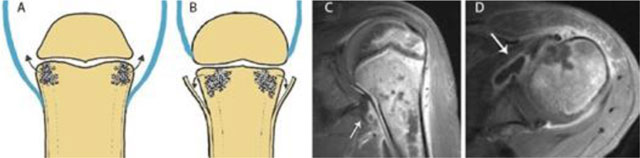

Figure 8

Joint contamination in osteomyelitis. Schematic drawings (a) and (b), coronal (c) and axial (d) T1–WI Fat–Sat after gadolinium contrast administration. (a) shows a joint in which the joint capsule (blue) is attaching underneath the growth plate. This intra-articular location of the growth plate may lead to rapid spread of infection into the adjacent joint. (b) shows a joint in which the joint capsule (blue) is attaching above the growth plate. An extra-articularly located growth plate protects against early joint contamination. (c, d). Example on MRI of a patient with rapid spread of the infectious focus to the adjacent left shoulder joint. Because the joint capsule of the shoulder insert below the growth plate, metaphyseal osteomyelitis may easily spread through the medial cortex directly into the joint resulting in synovial enhancement (white arrow).

Magnetic Resonance Imaging is the modality of choice for early detection of acute OM. Bone marrow changes are detected within three to five days after disease onset on Fat–Sat T2-weighted imaging (WI). OM can spread to the joint depending on the position of the joint capsule compared to the growth plate. An extra-articular location of the growth plate does not predispose to joint infection, whereas intra-articular position of the growth plate may cause rapid spread to the adjacent joint (Figure 8). Soft tissue extension, joint effusion, abscess formation and sinus tracts are accurately visualized. A pathognomonic sign for acute osteomyelitis is the presence of intramedullar fat globules on T1–WI. Islands of fat are released by necrotic lipocytes resulting in high signal intensity (SI) on T1–WI (Figure 9) [8910].